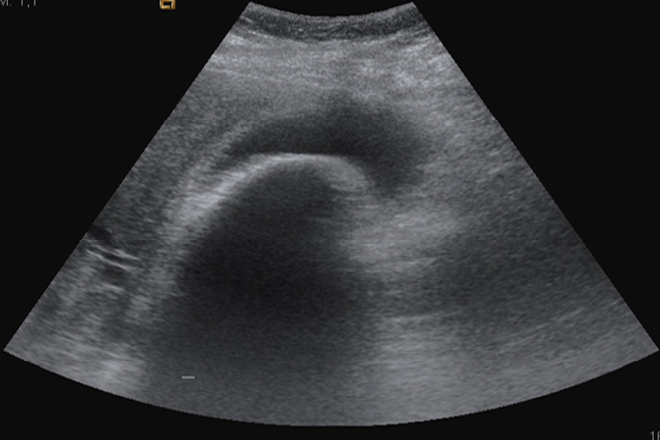

Prueba diagnóstica de elección ecografía abdominal, que muestra los cálculos como ecos fuertes con sombra posterior y que se movilizan con los cambios posturales del paciente. En ocasiones los pacientes con colelitiasis presentan síntomas atípicos de patología biliar (flatulencia, pirosis, distencion abdominal). Estos síntomas no suelen tener relación con la presencia de colelitiasis, por lo que se recomienda ampliar estudio etiológico.